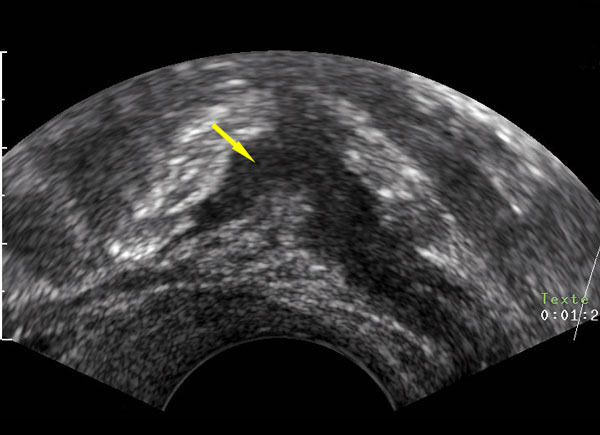

Échographie endovaginale en coupe sagittale passant en arrière du vagin montrant une masse hypoéchogène allongée remplaçant la musculeuse digestive typique d’atteinte endométriosique de la charnière recto-sigmoïde. Tiré de : Darai É, Bazot M, Ballester M. Endométriose. Rev Prat 2010;60:603-9.